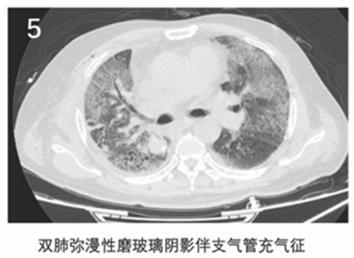

作者指出,2019新型冠状病毒肺炎有以下6个典型的CT影像学征像(图1~6):

(5)双肺弥漫性磨玻璃阴影伴支气管充气征;

(3)重症期:双肺弥漫性病变,少数呈"白肺"表现,实变影为主,合并磨玻璃影,多伴条索影,支气管充气征。